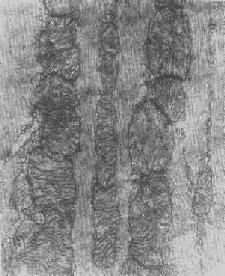

线粒体肿

图1-9 线粒体肿

2.大小改变 细胞损伤时最常见的改变为线粒体肿大。根据线粒体的受累部位可分为基质型肿胀和嵴型肿胀二种类型,而以前者为常见。基质型肿胀时线粒体变大变圆,基质变浅、嵴变短变少甚至消失(图1-9)。在极度肿胀时,线粒体可转化为小空泡状结构(图1-10,图1-11)。此型肿胀为细胞水肿的部分改变。光学显微镜下所谓的浊肿细胞中所见的细颗粒即肿大的线粒体。嵴型肿较少见,此时的肿胀局限于嵴内隙,使扁平的嵴变成烧瓶状乃至空泡状,而基质则更显得致密。嵴型肿胀一般为可复性,但当膜的损伤加重时,可经过混合型而过渡为基质型。